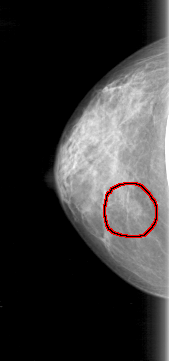

D_4085_1.LEFT_CC

LEFT_CC LINES 4681 PIXELS_PER_LINE 2326 BITS_PER_PIXEL 12 RESOLUTION 43.5 NON_OVERLAY

FILE: D_4085_1.RIGHT_CC.OVERLAY

TOTAL_ABNORMALITIES 1

ABNORMALITY 1

LESION_TYPE MASS SHAPE OVAL MARGINS OBSCURED

ASSESSMENT 0

SUBTLETY 3

PATHOLOGY BENIGN

TOTAL_OUTLINES 1

BOUNDARY